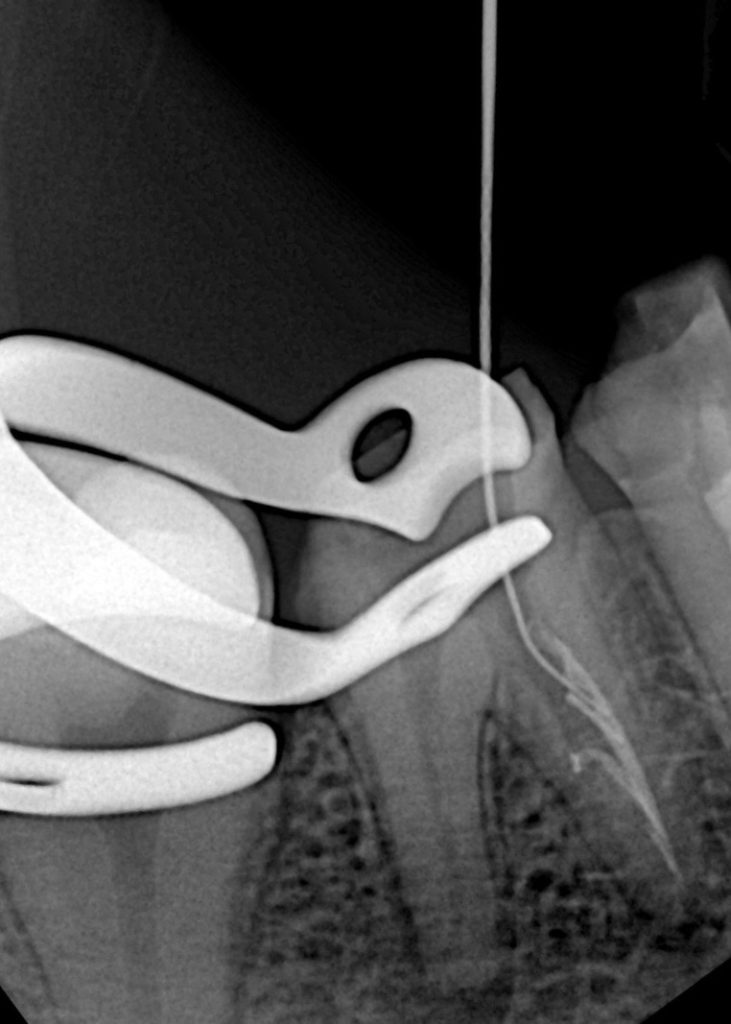

A mechanical ledge was identified in the mesial canal during negotiation. Glide path re-established with #08–10 K-files using watch-winding motion and chelating lubricant (RC-Prep). A small strip perforation was observed and sealed with ProRoot MTA (Fig 3).

- Fig 3: Bypassed ledge and MTA placed in perforation area.